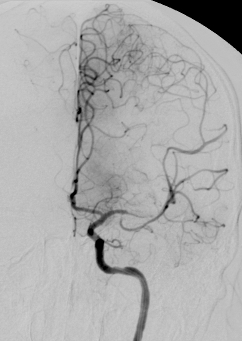

Angiographisch zeigte sich bei Anspritzen der linken A. vertebralis das gesamte innere Hirnvenensystem, V. Galeni, Sinus rectus und Sinus transversus rechts, verschlossen.

Da sich die Symptomatik trotz systemischer intravenöser Heparinisierung rasch verschlechterte, wurde die Indikation für eine lokale Thrombolyse gestellt. Zu diesem Zweck wurde transfemoral (venös) ein Mikrokratheter bis in das innere Hirnvenensystem durch den Thrombus vorgebracht.